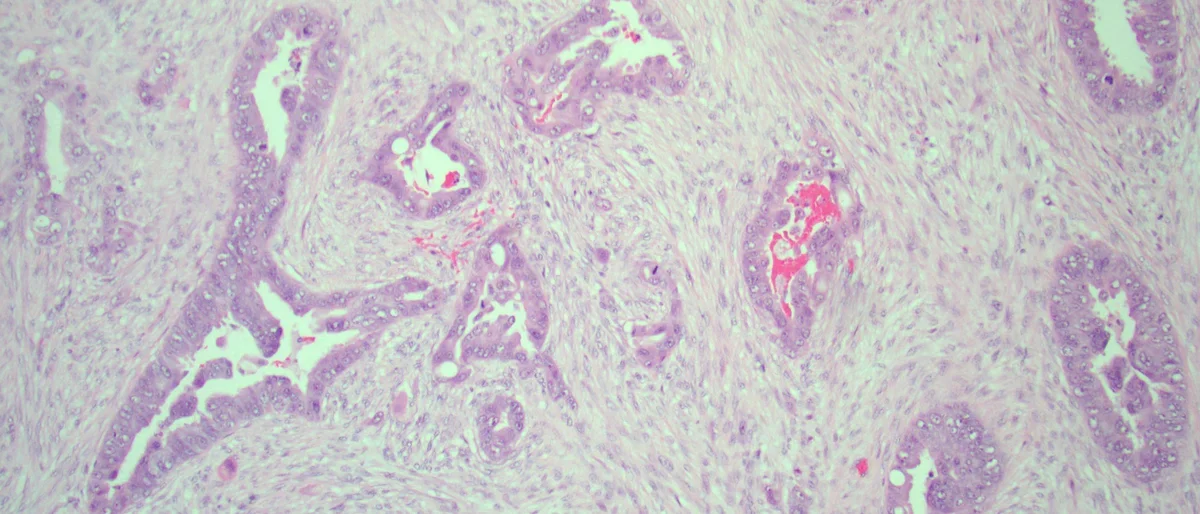

Pancreatic ductal adenocarcinoma

The main research focus of the Dawson Laboratory is pancreatic cancer, an aggressive and highly recalcitrant malignancy. We are seeking to better understand the molecular and cellular basis of pancreatic cancer in order to improve chemoprevention, early detection and therapeutic approaches. We are engaged in both basic and translational research that makes use of cell and animal-based models, as well as patient-derived clinical samples. Our lab is making progress in describing events that contribute to the evolution of pancreatic cancer, identifying biomarkers suitable for clinical decision making, and evaluating novel therapeutic strategies. We are located in the Department of Pathology and Laboratory Medicine in the David Geffen School of Medicine at UCLA.  We are also affiliated with the Jonsson Comprehensive Cancer Center and the UCLA Agi Hirshberg Center for Pancreatic Diseases.